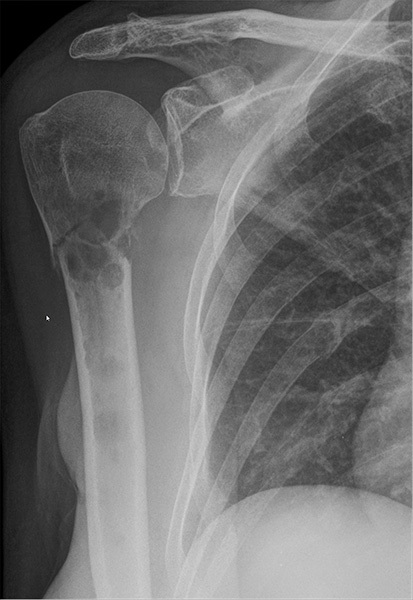

Diagnostic Studies. Medical imaging is the initial approach to suspect bony metastases. Plain radiography (X-ray), computed tomography (CT), magnetic resonance imaging (MRI), and single-photon emission computed tomography (SPECT) all are used for the diagnosis of metastasis.19 X-ray is the most cost-efficient and most readily available imaging modality, but it has limited sensitivity, typically only able to diagnose bony lesions greater than 1 cm or destruction of bone trabecular greater than 50%. (See Figure 1.)

Figure 1. Pathological Fracture of Right Proximal Humerus in a Patient with Metastatic Breast Cancer |

Other osteolytic lesions also are seen at the glenoid cavity and several ribs. Pathological fractures also are seen at the ribs (Courtesy of Hellerhoff - CC BY-NC-SA 4.0) - https://commons.wikimedia.org/wiki/File:Pathologische_Fraktur_Humerus_bei_Metastasen_Mammakarzinom_69W_-_CR_ap_-_001.jpg |